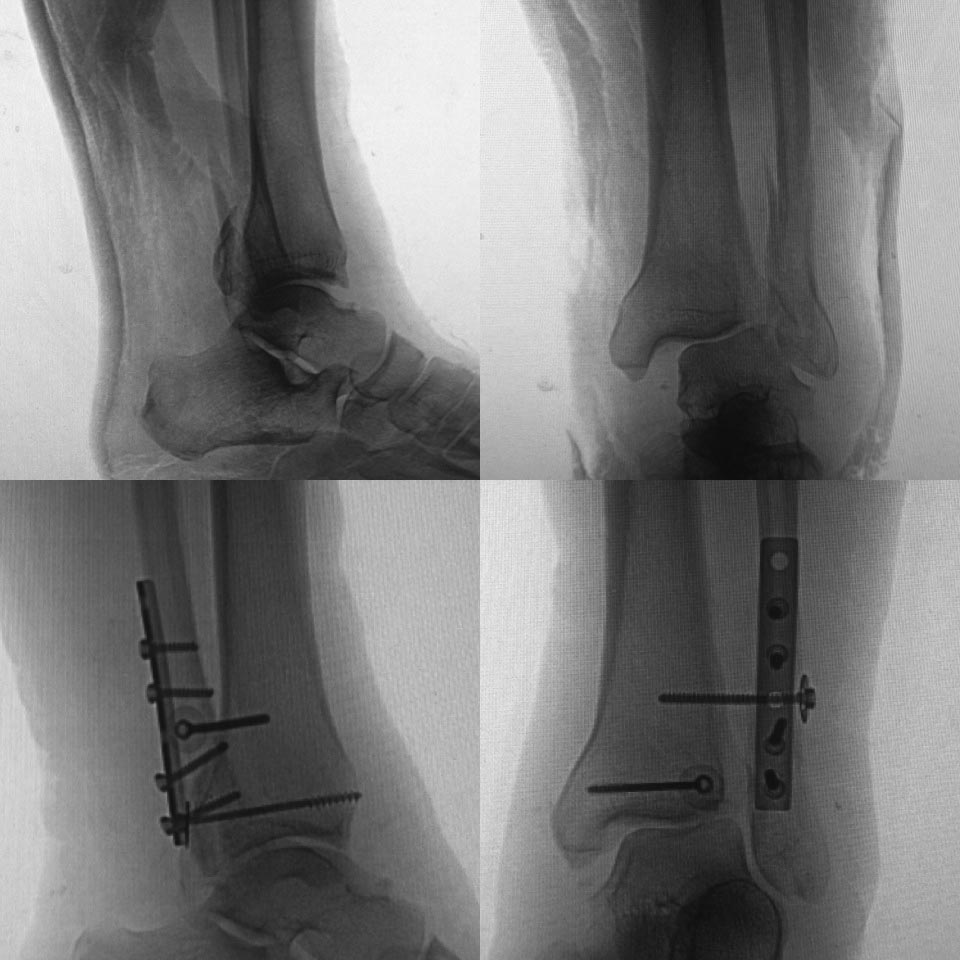

до/после

Мне кажется сращение малоберцовой состоялось, межберцовый диастаз сомнителен, задний край большеберцовой клинически незначим. Укорочение малоберцовой кости не менее 3 мм.

На снимочках до и после. Если после представленный снимок сразу после операции-то там уже явный подвывих кнаружи.Причина по-моему в том, что малоберцовая кость не адаптирована полностью в сулкусе синдесмоза ,а ротирована и в таком положении стянута винтом.Так что єтап зачистки рубцов в пространстве синдесмоза обязателен.Ну и фиксация с усранением ротации малоберцовой кости 2-мя винтами.